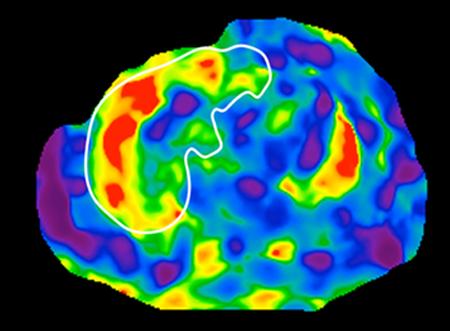

image: Magnetic resonance elastography (MRE) scan of the liver showing elevated liver stiffness consistent with cirrhosis. MRE is a non-invasive, imaging-based biomarker for detection of cirrhosis.

Then the team identified 27 unique bacterial features unique to the gut microbiomes, and thus stool, of people with NAFLD-cirrhosis. The researchers were able to use this noninvasive stool test to pick out the people with known NAFLD-cirrhosis with 92 percent accuracy. But more importantly, the test allowed them to differentiate the first-degree relative with previously undiagnosed NAFLD-cirrhosis with 87 percent accuracy. The results were confirmed by magnetic resonance imaging (MRI).